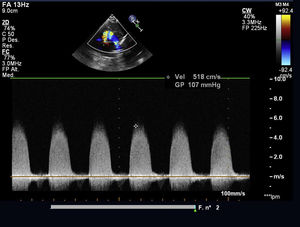

Caso clínicoDatos preoperatoriosRecién nacido a término sin antecedentes gestacionales de interés, diagnosticado de estenosis valvular aórtica a los 2días de vida tras auscultación de soplo cardiaco, con válvula aórtica displásica (fig. 1). En los primeros controles ecocardiográficos se describía una estenosis moderada que, sin embargo, presentó una rápida progresión en las primeras semanas de vida hasta alcanzar criterios de severidad. Se remite al paciente a nuestro centro con gradientes pico/medio por Doppler entre 96/52mmHg y hasta 150/80 según el estudio (fig. 2), sin insuficiencia aórtica y con ventrículo izquierdo (VI) con hipertrofia concéntrica ligera y buena función sistólica. El anillo aórtico era de 7mm, lo que representaba un Z score normal para su peso. Dada la evolución de la estenosis se decide programar la cirugía de forma preferente con el paciente en situación clínica estable.